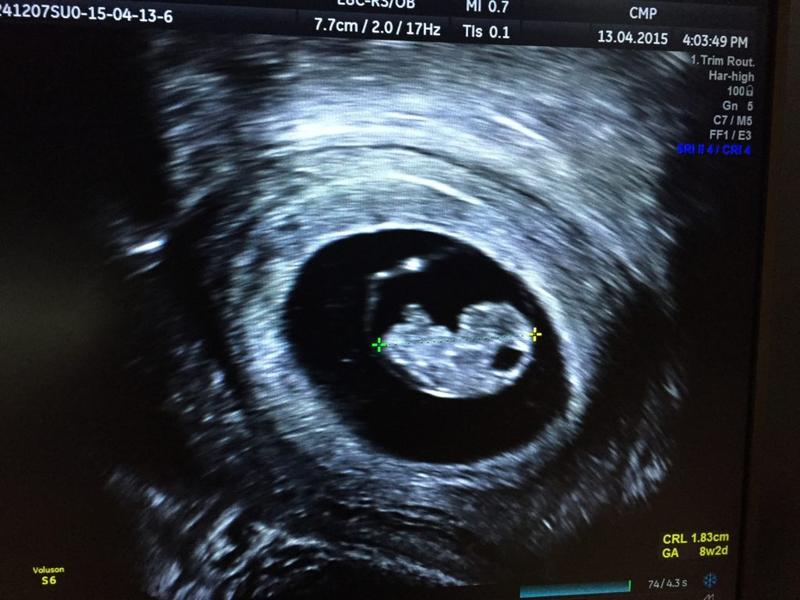

5 tydzień ciąży